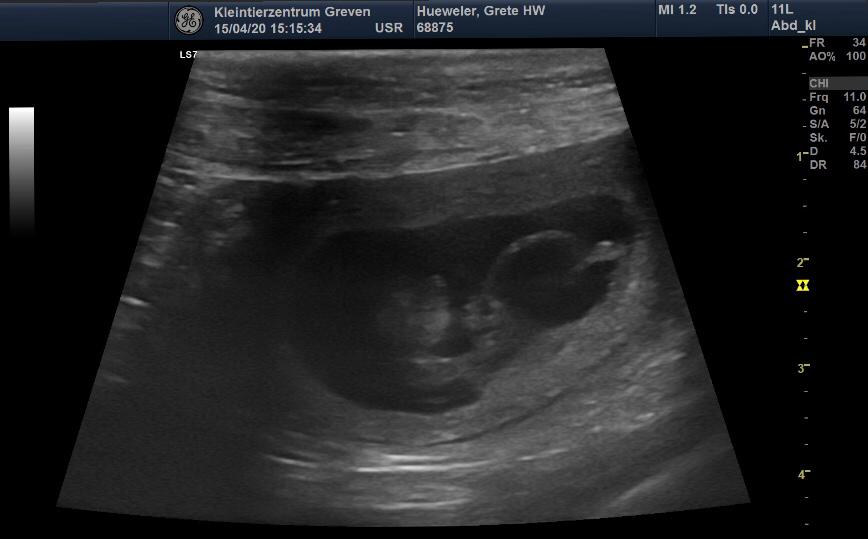

Juhuuu Grete ist trächtig. Wir freuen uns sehr. Es sind mehrere Fruchtanlagen zu erkennen. Die Welpen werden um den 20 Mai erwartet.